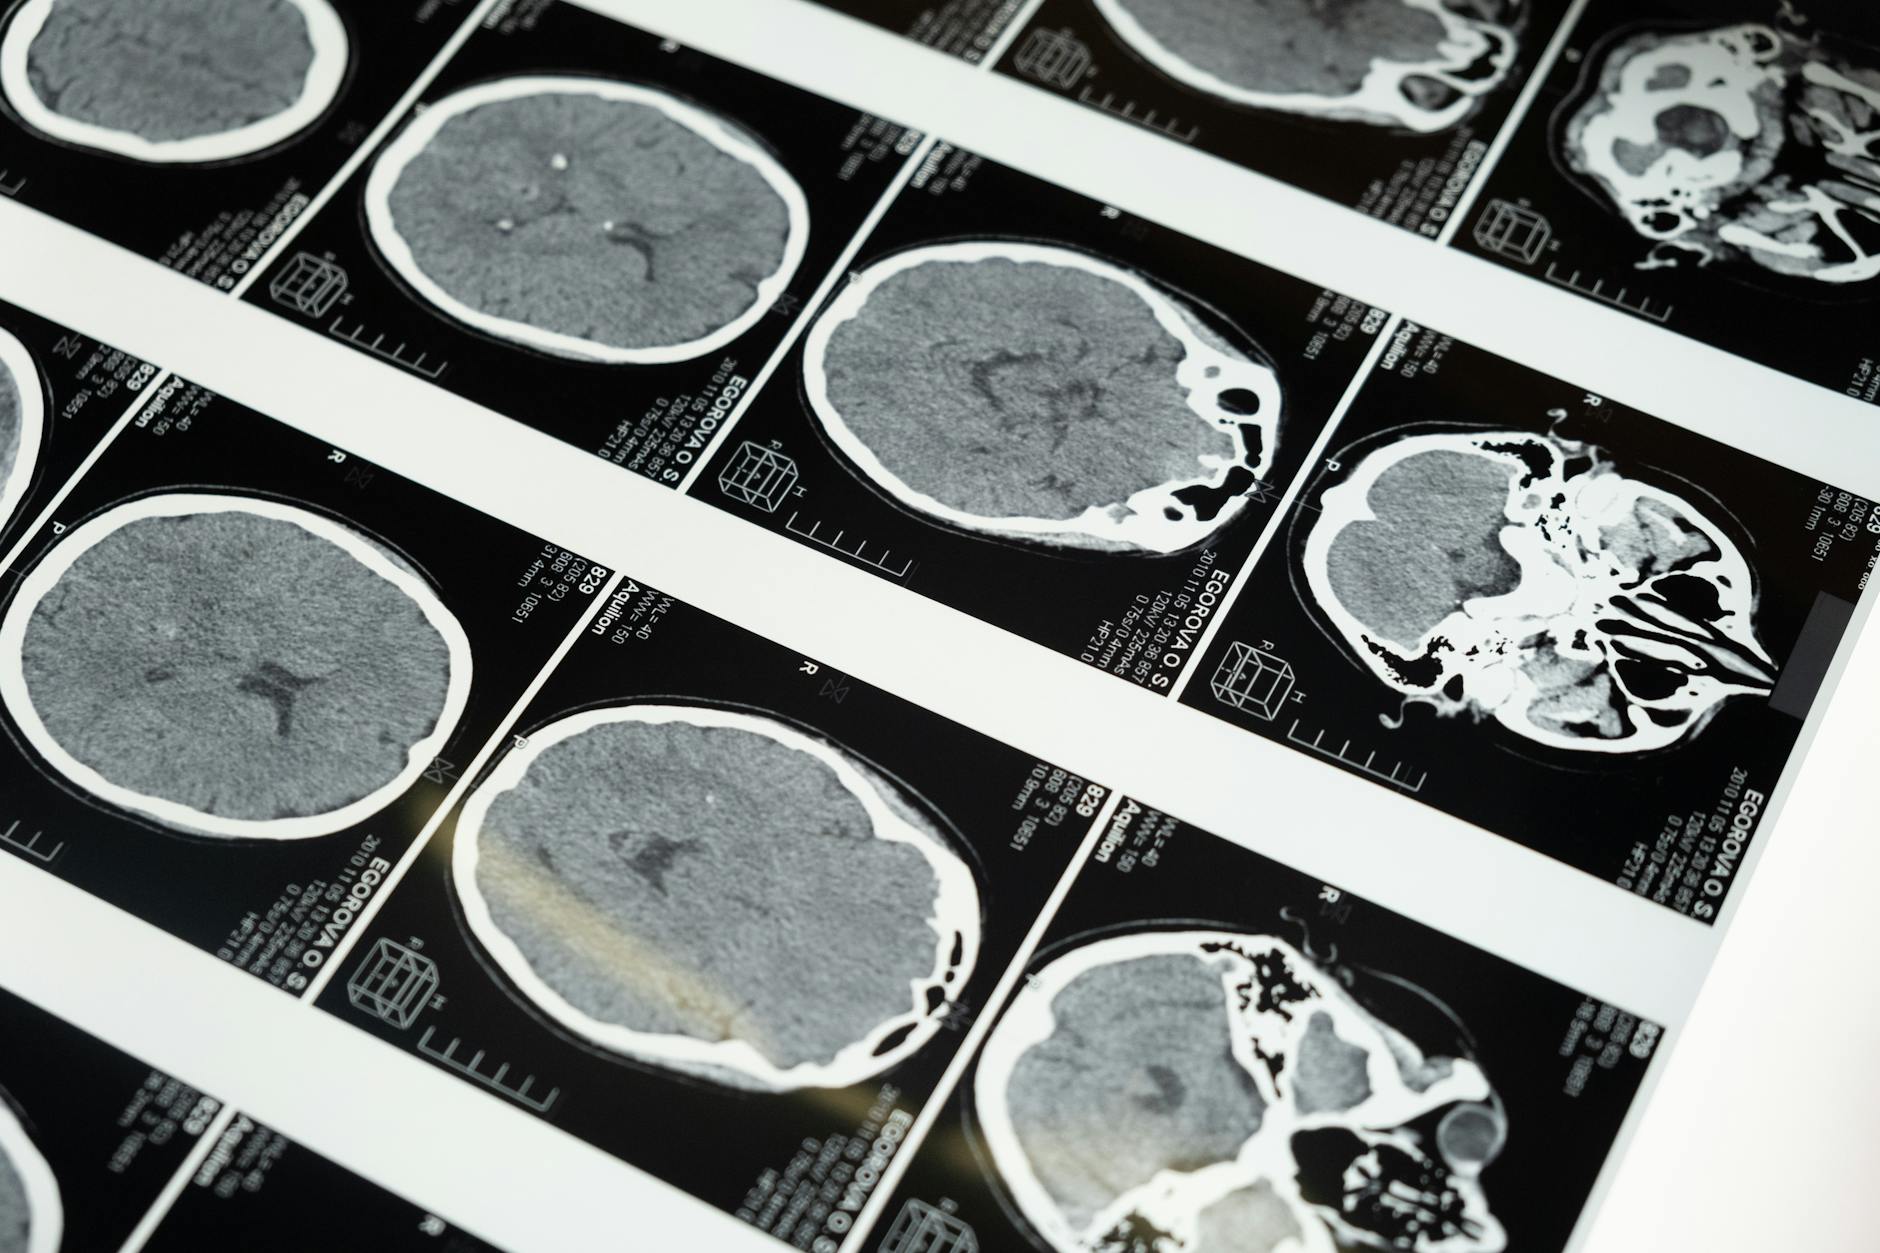

Fotos: WikipediaInvestigadores descubrieron que los niveles de vitamina D en la mediana edad pueden influir en la salud cerebral décadas después. En un estudio que siguió a casi 800 personas durante 16 años, aquellos con niveles más altos de vitamina D en sus 30 y 40 años tuvieron niveles más bajos de proteína tau más tarde, un marcador clave vinculado a la demencia.

Esto sugiere que la vitamina D podría desempeñar un papel más importante en la salud cerebral a largo plazo de lo que se pensaba anteriormente. La proteína tau es un indicador clave de la enfermedad de Alzheimer y otras formas de demencia.